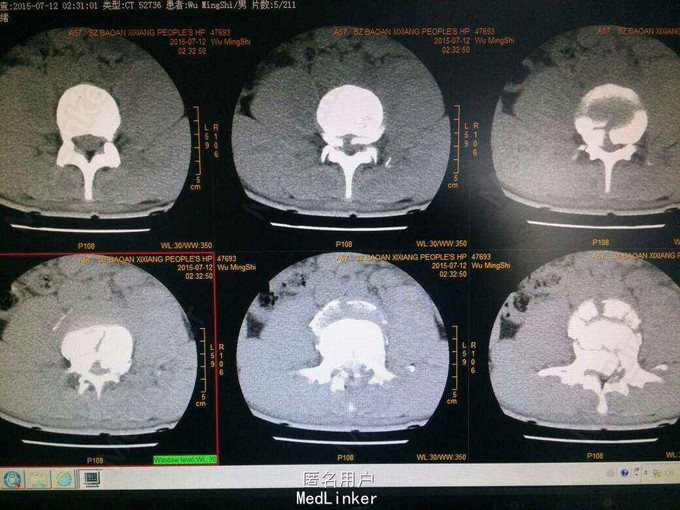

查:腰部后凸畸形,压痛,叩痛,腰3平面以下痛觉减退,肌力:胫前肌:左I级,右IIl级,提睾反射消失。CT:腰3椎体爆裂性骨折,腰2椎体前滑脱。椎管严重占位。

腰3椎体爆裂性骨折并双下肢不全瘫 手术后路椎管减压,椎弓根固定,腰3椎体骨折复位,后外侧植骨,椎管探查,硬膜修补。 术后脱水,激素,神经营养,二便及下肢功能康。 术后影像表现腰3椎体后移骨块复位。